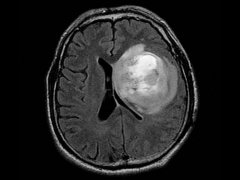

脑肿瘤能活多久?治疗方法决定了

脑肿瘤 能活多久?对于脑肿瘤以及颅内占位性病变等神经外科疾病...